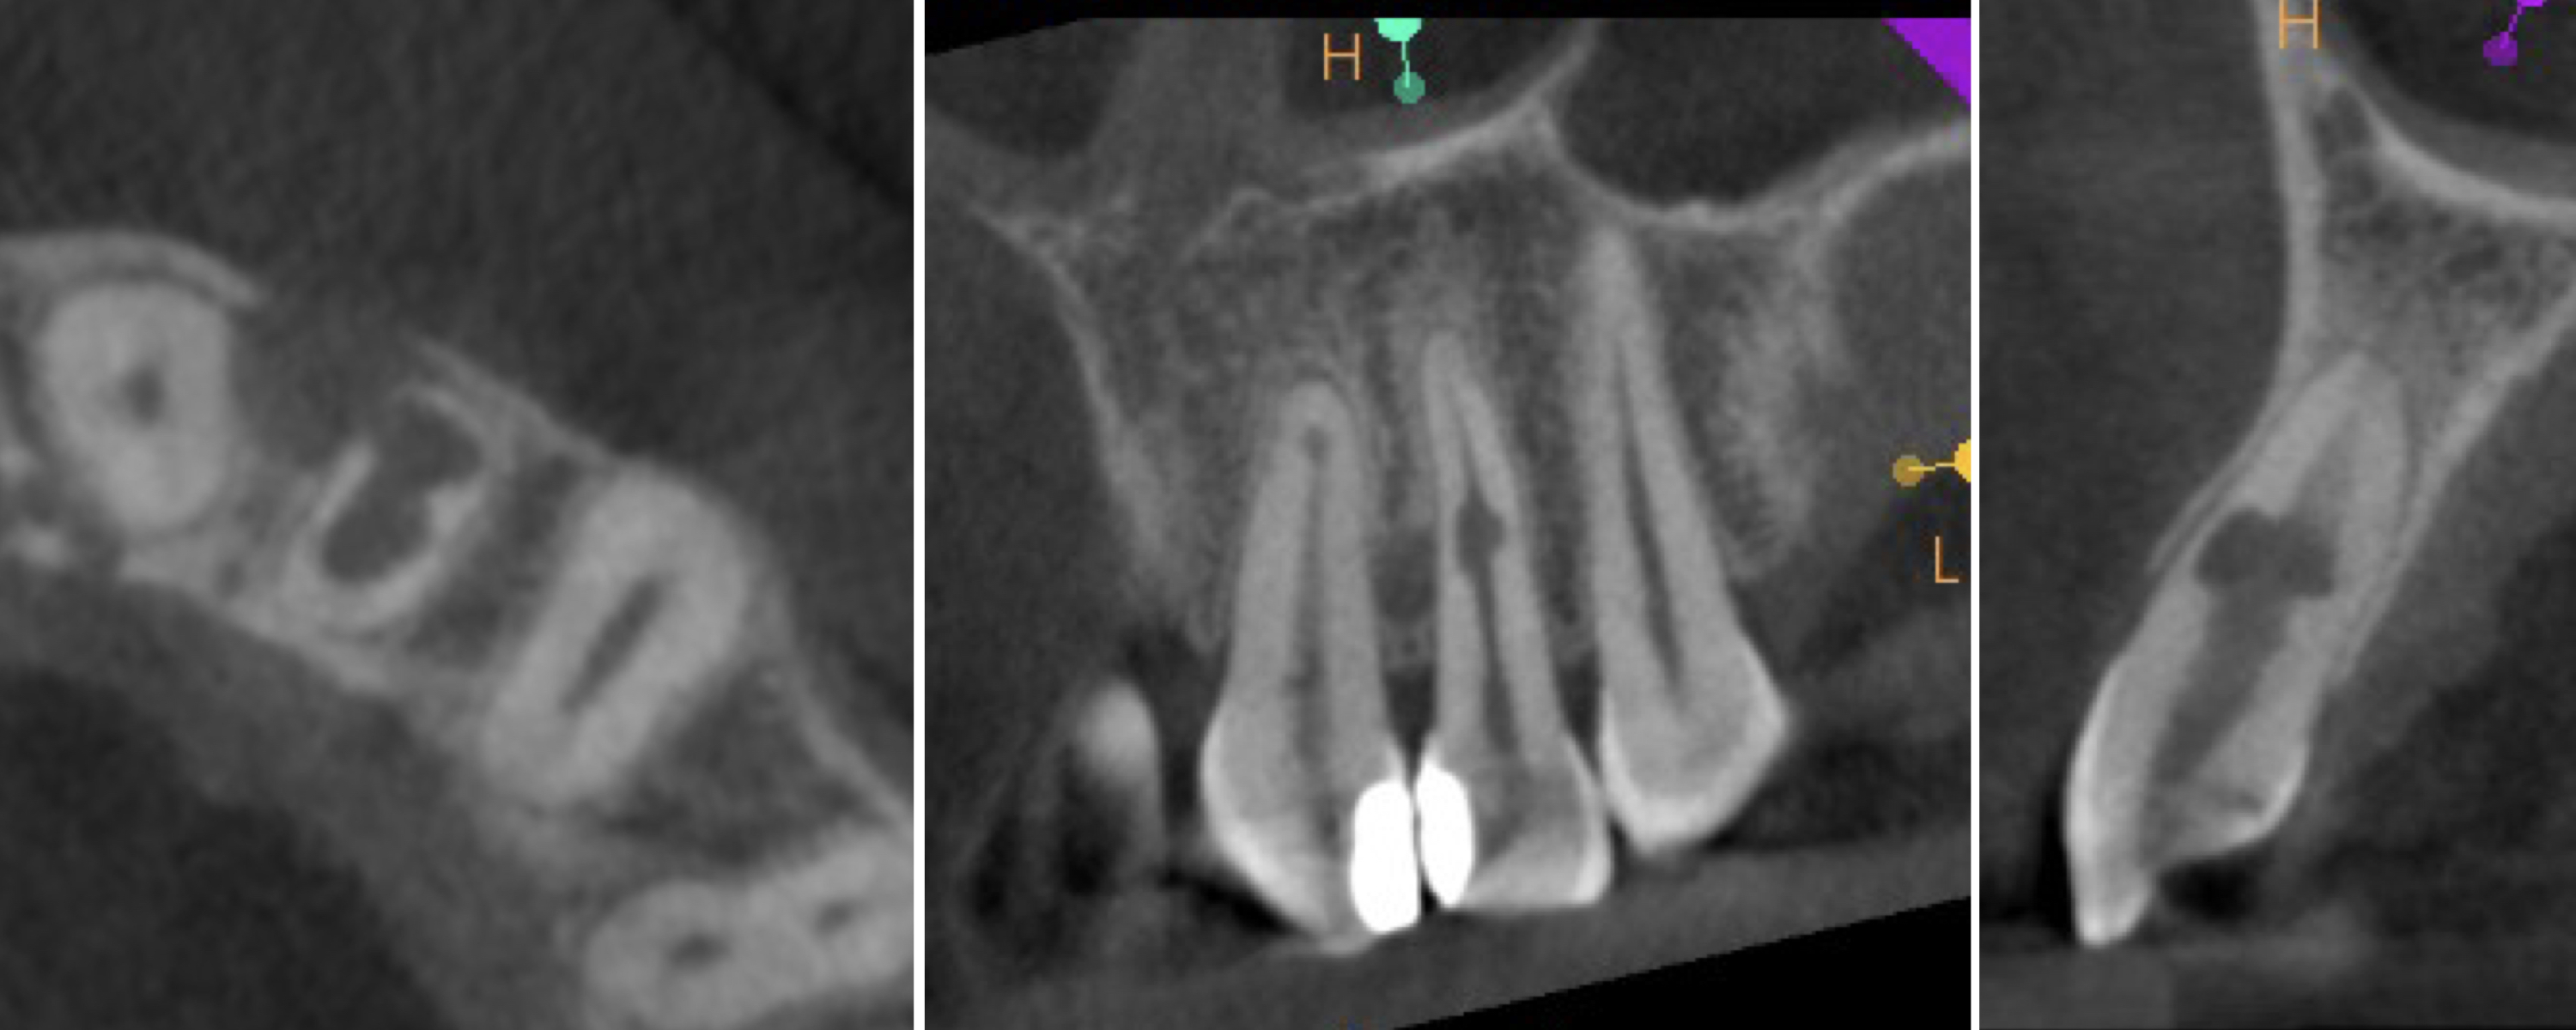

A 28-year-old patient was referred to the endodontic office after diagnosis of inflammatory IRR in the maxillary right central incisor on a periapical radiograph. A CBCT scan was taken to determine the prognosis and to plan the treatment (Figs. 8a-e). The 3D image revealed perforation of the labial wall of the root and destruction of the bundle bone surrounding the resorption cavity.

Fig. 8c: Radiograph (a) and CBCT scan (b–e) taken before the treatment, showing the root perforation and perforation of the cortical bone.